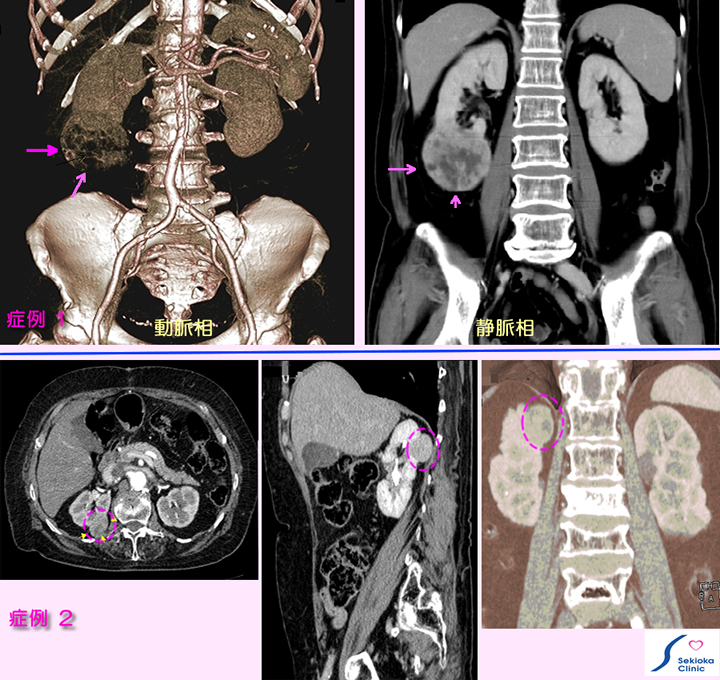

腎臓がん

血尿・痛みなどなく、腎以外の症状で検査し、偶然見つかる。症例2も自覚症状無く偶然見つかる。

症例1は他の目的での腹部CT検査時、腎がん疑われ、造影MDCTで精査。右腎下極に腫瘍(矢印)を認めるが他に転移所見を認めず。症例2は血管の造影検査時、偶然見つかる。比較的小さな早期の腎臓がん(破線円内)です。

手術にて摘出。手術時転移は認めず、2年無事に経過。